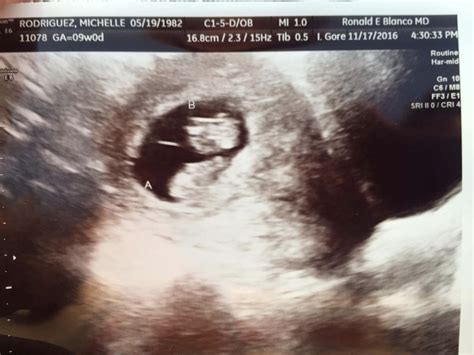

During the Ultrasound 9 Weeks Twins scan, the ultrasound technician will use a transvaginal probe to get a clear view of the uterus. This method provides a more detailed image compared to the transabdominal approach, especially at this early stage. The procedure is generally painless, although some women may experience slight discomfort. The technician will measure the size of each embryo and check for a heartbeat, which is usually detectable by this week.

• Confirmation of two gestational sacs.

• Measurement of the crown-rump length (CRL) of each embryo.

• Detection of fetal heartbeats.

• Assessment of the placenta and amniotic sacs.

Two distinct gestational sacs Indicates dizygotic (fraternal) twins.

Single gestational sac with two yolk sacs Indicates monozygotic (identical) twins.

Detectable heartbeats Confirms the viability of the embryos.